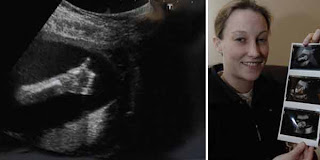

Ajaib, Janin Acungkan Jempol - Berita Harian, Sungguh tak diduga ketika seorang ibu yang tengah hamil ini melakukan pemeriksaan kandungannya yang dilakukan secara berkala, ia melihat janinnya sedang mengacungkan jempol. Janin tersebut terlihat saat sang ibu yang bernama Donna Sayer (29) itu melakukan dua kali pemindaian di rumah sakit di Canterbury Kent beberapa minggu setelah ia dinyatakan hamil. Donna bersama pasangannya, Simon Biscoe, khawatir karena kepala bayi tampak lebih panjang dengan tubuh terlalu kecil.

Ketika Donna melakukan pemindaian ketiga, Donna dan Simon sangat senang dengan hasil yang menyatakan bahwa janin di dalam kandungannya menunjukkan kepala bayi sudah mencapai ukuran normal dan tidak mengalami masalah medis. Namun, yang mengejutkan dari pasangan ini ialah foto janin yang sedang mengacungkan jempolnya. Melihat keanehan terebut, Donna bersama perawat tertawa saat menyadari bayi itu mengacungkan jempol. "Setelah memeriksa semuanya baik-baik saja, perawat mencoba mengambil beberapa foto tambahan," ujar Sayer yang seorang manajer makanan dan minuman di Kent County Cricket Club.

Meskipun bayi itu tampak bersembunyi, ia memberikan acungan jempol seolah ingin memberitahu banyak orang bahwa dirinya baik-baik saja, kata Sayer lagi. Fay Smith praktisi USG di William Harvey Hospital mengatakan, "Anda bisa melihat bayi sering menghisap jempol atau melakukan beberapa gerakan kasar. Sering pula mereka berkedip. Saya sering tertawa dengan para calon orang tua saat bayi mereka tampak menyembunyikan bagian tubuh pribadi.”